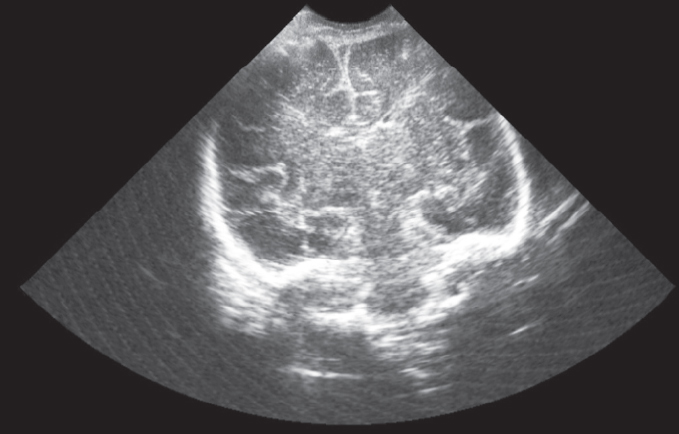

Clinical observation. This article presents the results of observing two women with premature amniotic fluid expulsion at 22 and 24 weeks’ gestation, respectively. In the first case, the woman was immediately admitted to the perinatal center; in the second observation, she was admitted after 3.5 weeks of treatment at another institution. In both cases, pregnant women had manifestations of oligo and endotoxemia, a protective inflammatory response in the mother-placental-fetal system (more pronounced in the second observation) against a background of urogenital infection. In the course of complex treatment, the patients underwent detoxification, of efferent therapy in the form of repeated consecutive sessions of plasmapheresis, hemosorption (one operation each), external photomodification of blood with ultraviolet, laser beams with prolongation of pregnancy by 10 and 8 weeks. The deliveries in both cases were operative with live babies with body weight of 1600 g and 1840 g, respectively. In the first case the infant did not need intensive care, was breastfed, in the second observation the newborn received active respiratory support for 9 days, in the dynamics his condition normalized. No septic complications in mothers and fetuses were observed.